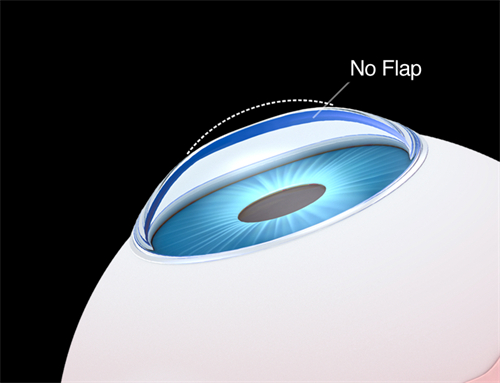

视网膜脱落的治疗方法有多种。对于尚未发生脱离的视网膜裂孔,可采用激光治疗,利用激光封闭裂孔,防止视网膜脱落。传统的巩膜环扎术和巩膜外加压术,适用于单纯的早期视网膜脱离。

而对于病情复杂的视网膜脱落,如伴有玻璃体混浊、牵拉等情况,玻璃体切割视网膜复位联合手术是常用的治疗方式。

这种手术对技术要求高,需要特殊的设备及术后护理。此外,渗出性视网膜脱离主要以治疗原发病为主。